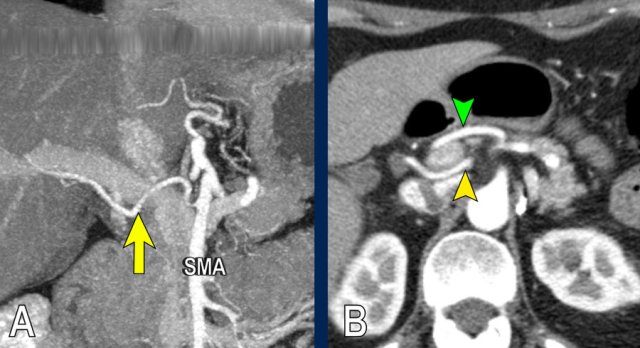

The use of multiplanar reformations improves overall CT performance as seen in this case.

A coronal reformat shows a small tumor in the pancreatic head (arrowheads) with obstruction of the common bile duct.

There seems to be just limited contact with the portal vein (arrow).

Continue with the next images.

A multiplanar reformat perpendicular to the portal vein shows that there is more extensive contact with the portal vein, 90 – 180 degrees (arrow).

Without contour irregularity this is classified as borderline resectable according to the DPCG criteria but resectable according to the NCCN criteria.

Resection without venous reconstruction proved to be R1, meaning presence of microscopic tumor invasion of the resection margin.